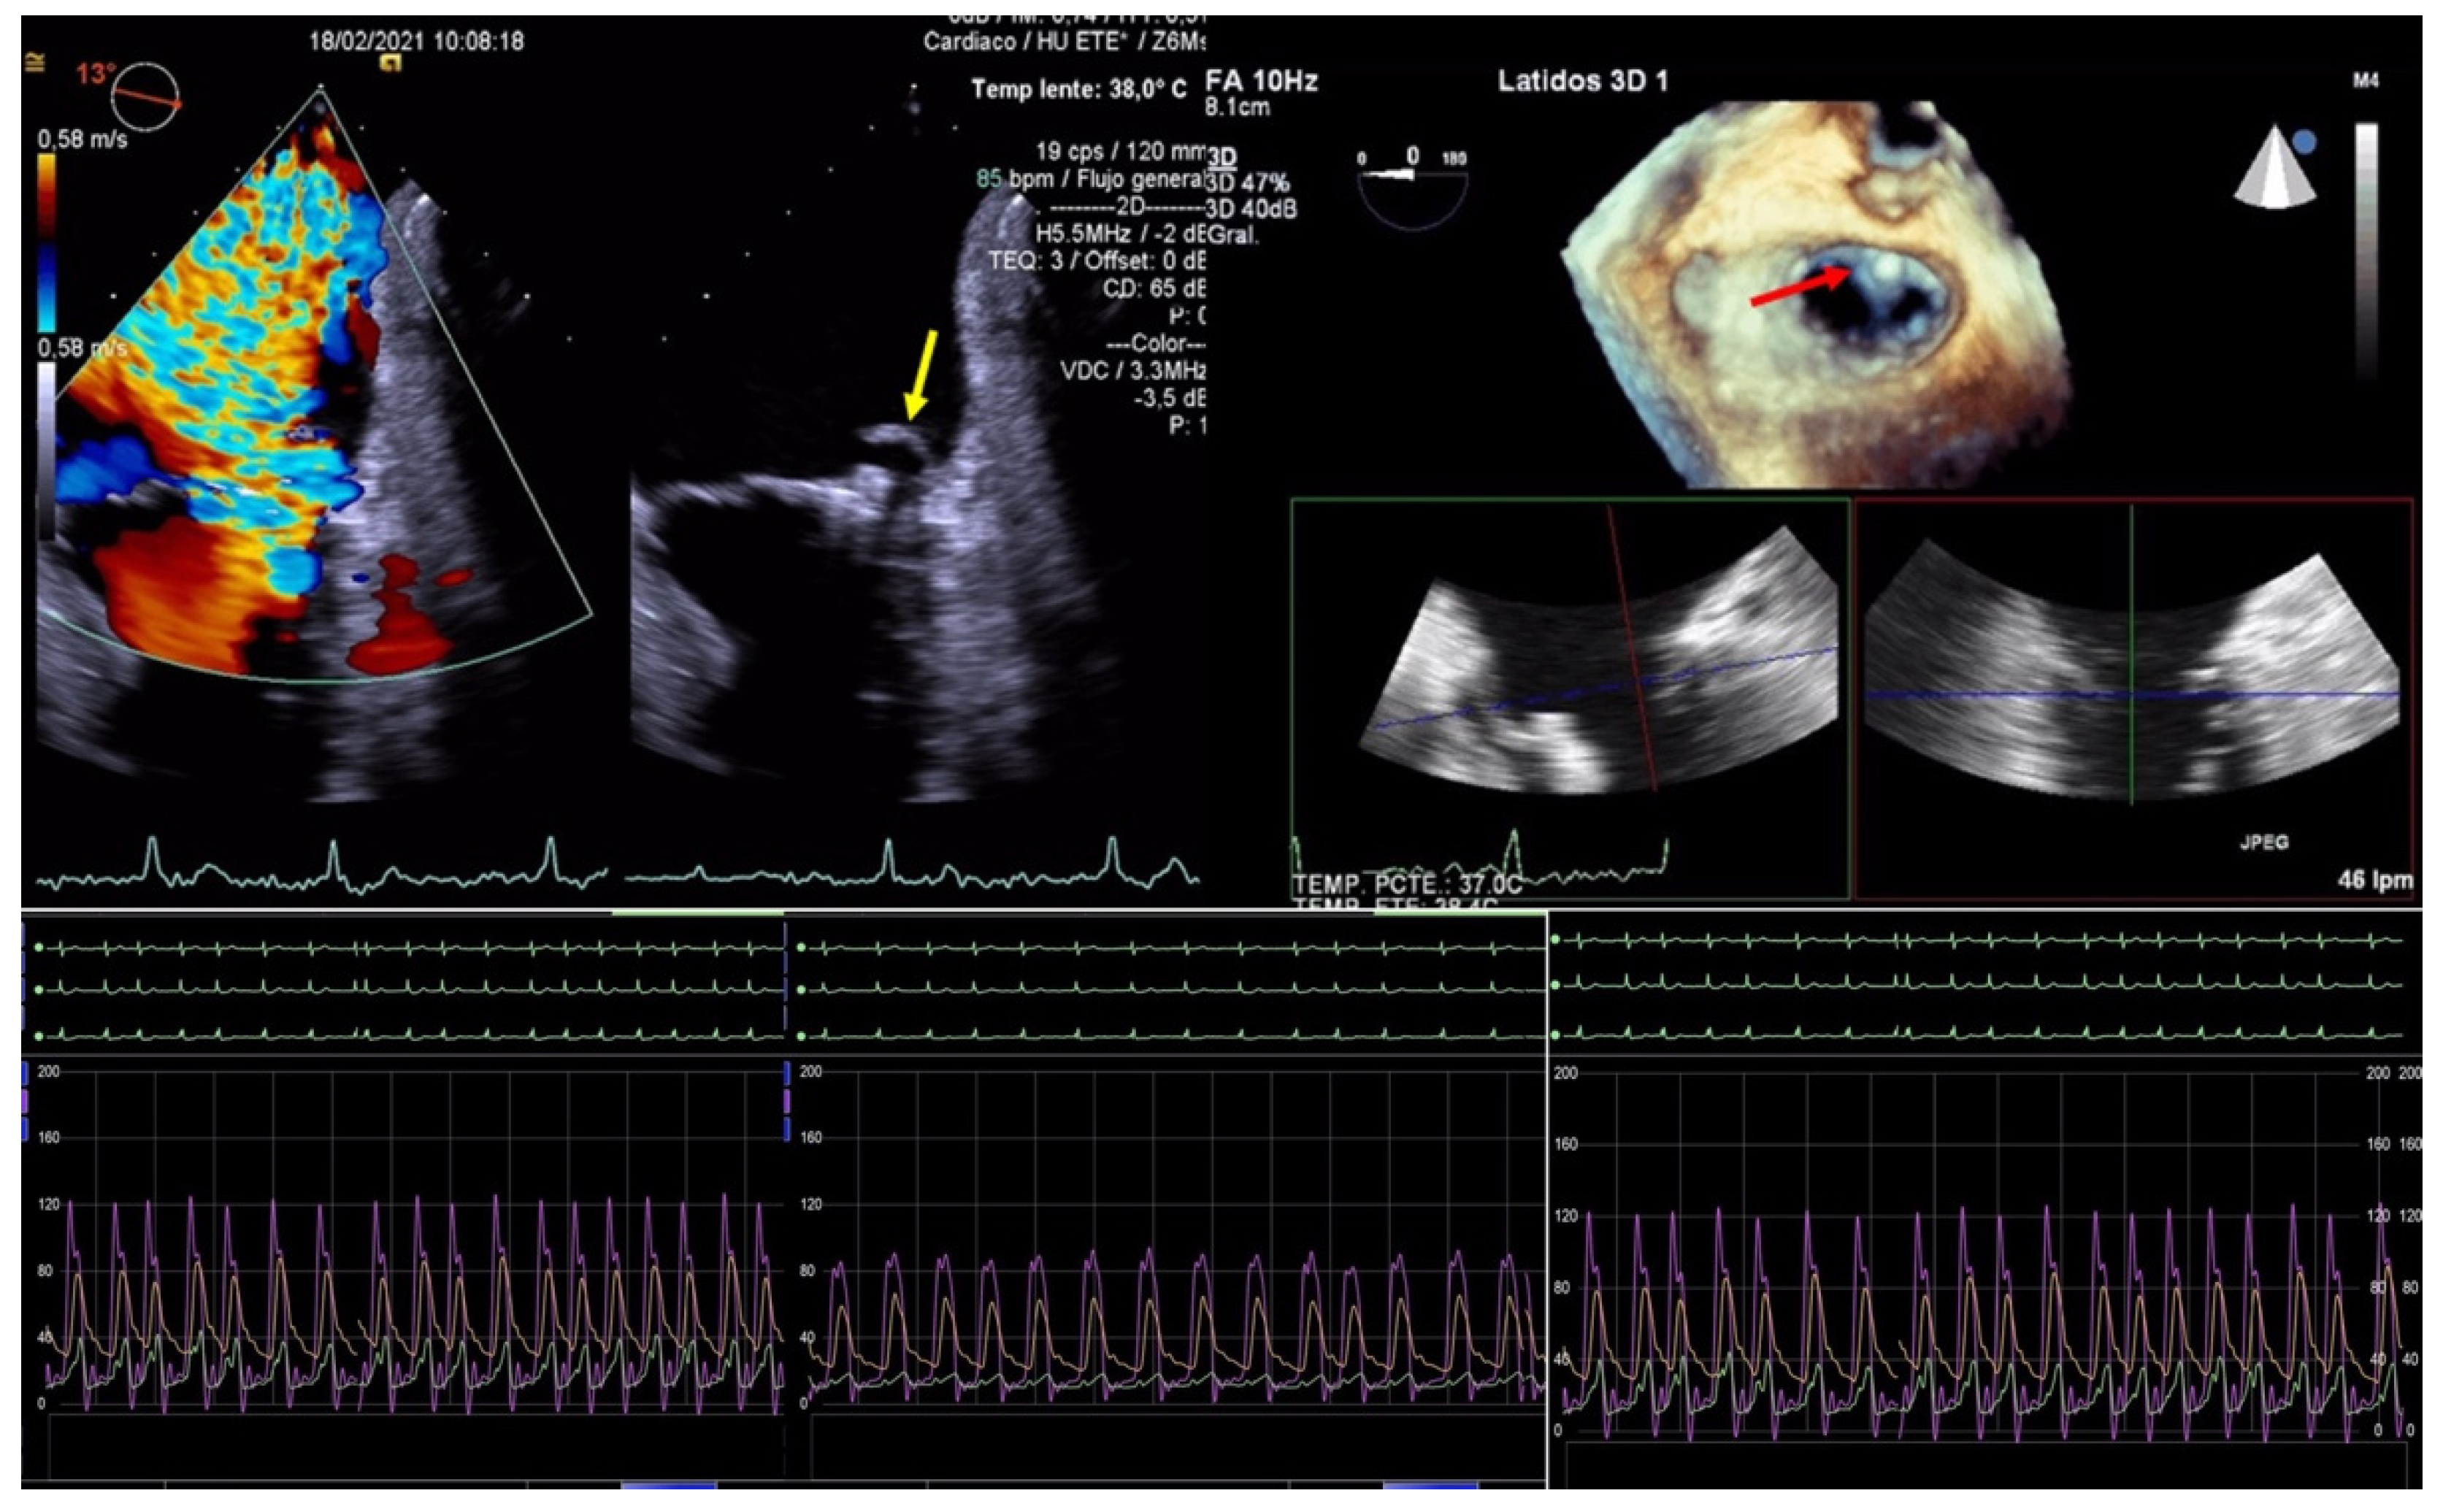

The echocardiographic criteria to diagnose SLDA are the color Doppler demonstration of significant MR through the leaflet interface, new excessive leaflet mobility following device deployment, and a lack of diastolic tissue bridge by 3DTEE; acute changes in pressure also occur with the new appearance of the v-wave after the initial improvement after clip implantation (Figure 5). Once the complication has occurred, the TEE undoubtedly helps in determining the mechanism of the loosening of the leaflet by measuring the portion of the free leaflet with respect to the measurement prior to implantation [13]. Other mechanisms, such as tear or perforation, can be viewed as a disruption of leaflet integrity reaching the leaflet edge or not, respectively. An excessive clip–leaflet tension can be shown as a shape distortion affecting leaflet coaptation, without disruption of the leaflet integrity. The entrapment of the clip in leaflets or subvalvular structures with chordal rupture appears in TEE as new excessive leaflet mobility [1]. Chordal entanglement should be avoided by minimizing device manipulation below the mitral valve and not advancing the system deep into the left ventricle.

Figure 5.

Two-dimensional transesophageal echocardiogram showing a very severe mitral regurgitation after the partial detachment of a clip and a leaflet tear prolapsing in the left atrium (yellow arrow). Three-dimensional transesophageal echocardiogram in the enface mitral view, where a clip can be seen attached to the anterior leaflet (red arrow) and loose from the posterior with a lack of diastolic tissue bridge. In the lower panel, simultaneous recording of left atrium (green), pulmonary artery (yellow), and aortic pressure (purple): baseline, post clip implantation and after detachment.